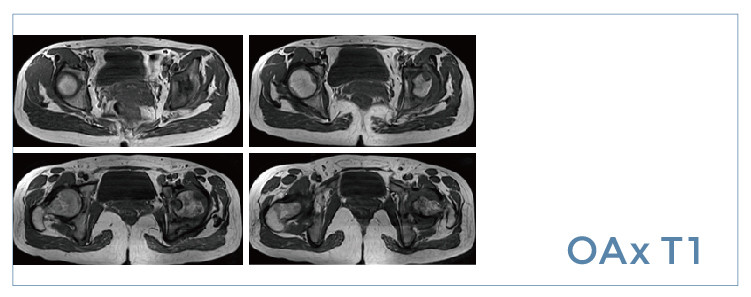

【朗润影像档案】磁共振影像病例分享(编号20190809)